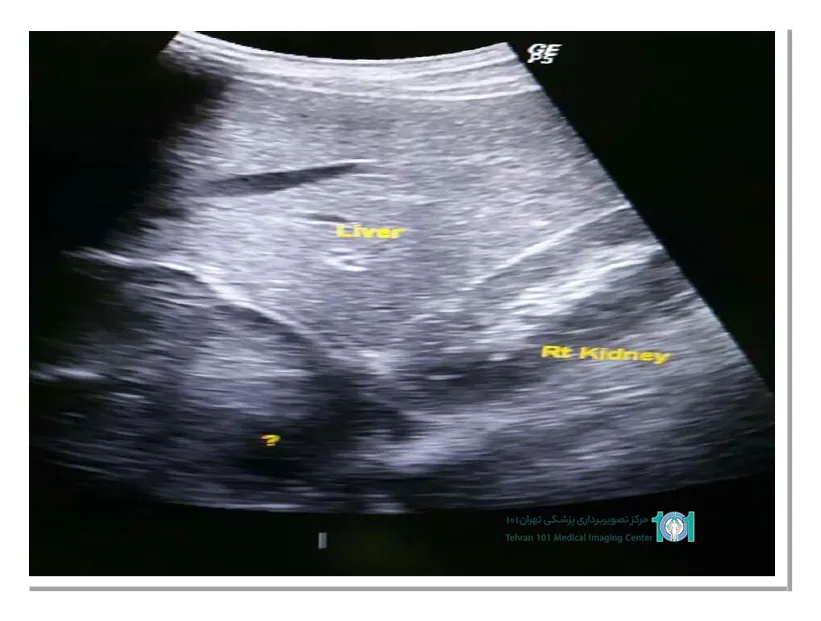

اکوژن در سونوگرافی چیست و چه مفهومی دارد؟

شاید از خود بپرسید دلیل اکوژن در سونوگرافی چیست؟ توده اکوژن در سونوگرافی پزشکی بیشترین سطح بازتاب را دارد، به عبارت دیگر، اکوژنیته بیشتری دارد. در تصاویر سونوگرافی، بافتهای اکوژن به رنگ سفید یا روشن نمایش داده میشوند.

در سونوگرافی پزشکی، تودههای اکوژن ممکن است نشانهای از وجود تغییرات غیرطبیعی در بافت باشند. به عنوان مثال، تودههای اکوژن در قلب جنین ممکن است نشانهای از اختلالات قلبی باشند، در پستان ممکن است نشانگر وجود تودههای خوش خیم یا بدخیم باشند و در رحم ممکن است نشانگر وجود فیبرومها یا تودههای دیگر باشند. اگر به بررسی دقیق اکوژنسیته در نتایج سونوگرافی نیاز دارید، میتوانید از خدمات پیشرفته سونوگرافی در تهران در بهترین مرکز معتبر تصویربرداری بهره ببرید.

اگر پزشک شما تودهای اکوژن را در هر قسمتی از بدن تشخیص داد، احتمالاً نیاز به بررسیهای دقیقتر برای تعیین نوع و خطرات احتمالی آن دارید.